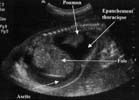

L'échographie met en évidence une masse intra-thoracique [7] :

A ces signes directs peuvent s'associer :